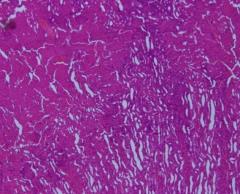

Microscopic examination of kidney:

Sections show renal tissue composed of cortex and medulla. Glomeruli are within normal limits. Severe degree of ATN is seen. Vascular structures are distributed evenly. No evidence of granuloma or malignancy is seen in any of the sections examined.

Fig. 1: Microscopic examination of male rabbit’s heart, stomach, liver and kidney tissues treated with S. nigra extract